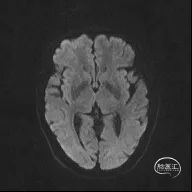

颅脑MR:脑内多发缺血灶、软化灶。